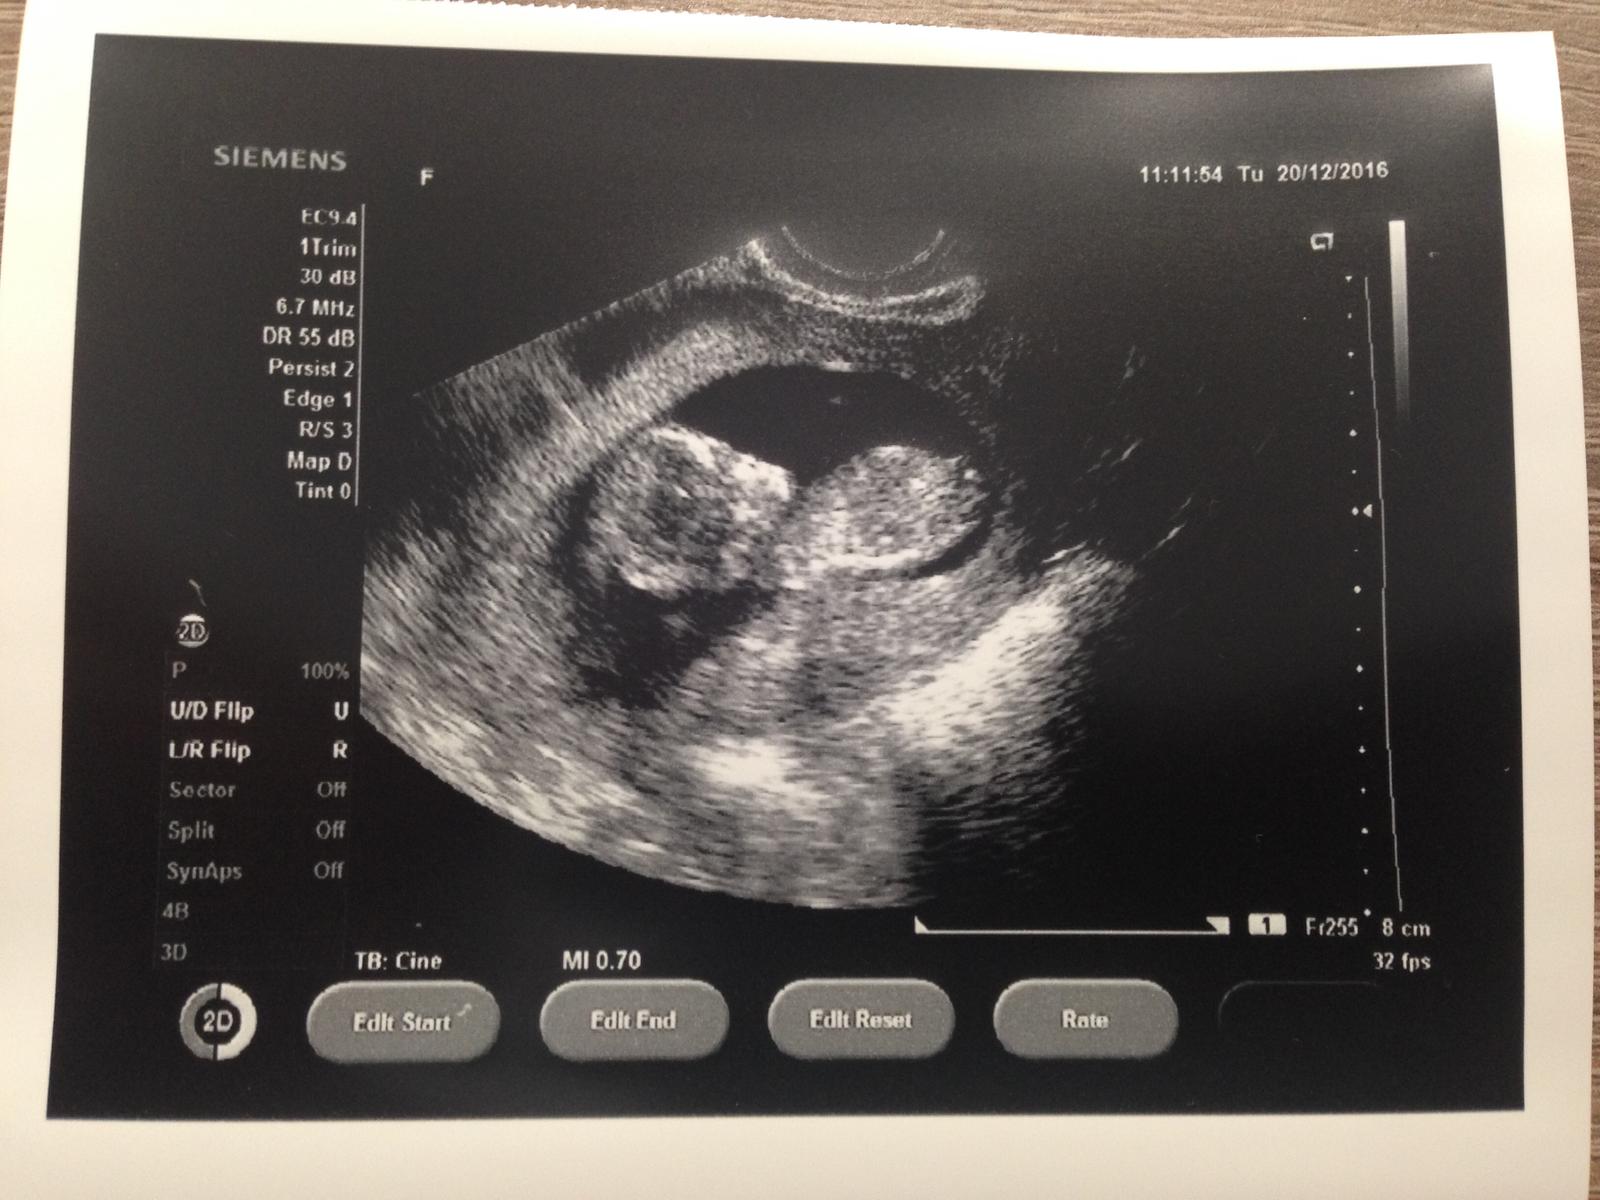

ahojte kocky nase @karmela @luta13 a @miriamn76 ideme Vas s drobcekom trosku pozdravit, dnes sme mali poradnu a uz mame 5,4cm 🙈👶🏼❣bubak moj rastie ako zvody 😬a mame vsetucko v poriadku ,sme prebiehajuci 13tt a termin mame zatial na 2.7.17 a dnes na sone pan dr.vylucil Downov syndrom ,oodla merania nosnej kosticky a sije takzeeee sme uuuuuplne zdravyyyy KLOP KLOP KLOP🙏🏻🍀👶🏼

a tu sme v plnej parade .. kym nas dr odfotil ,lebo sme velmiiiii aktivny v brusku 😍aaaaa? mame uz aj oficialne TEHU KNIZKU 😝